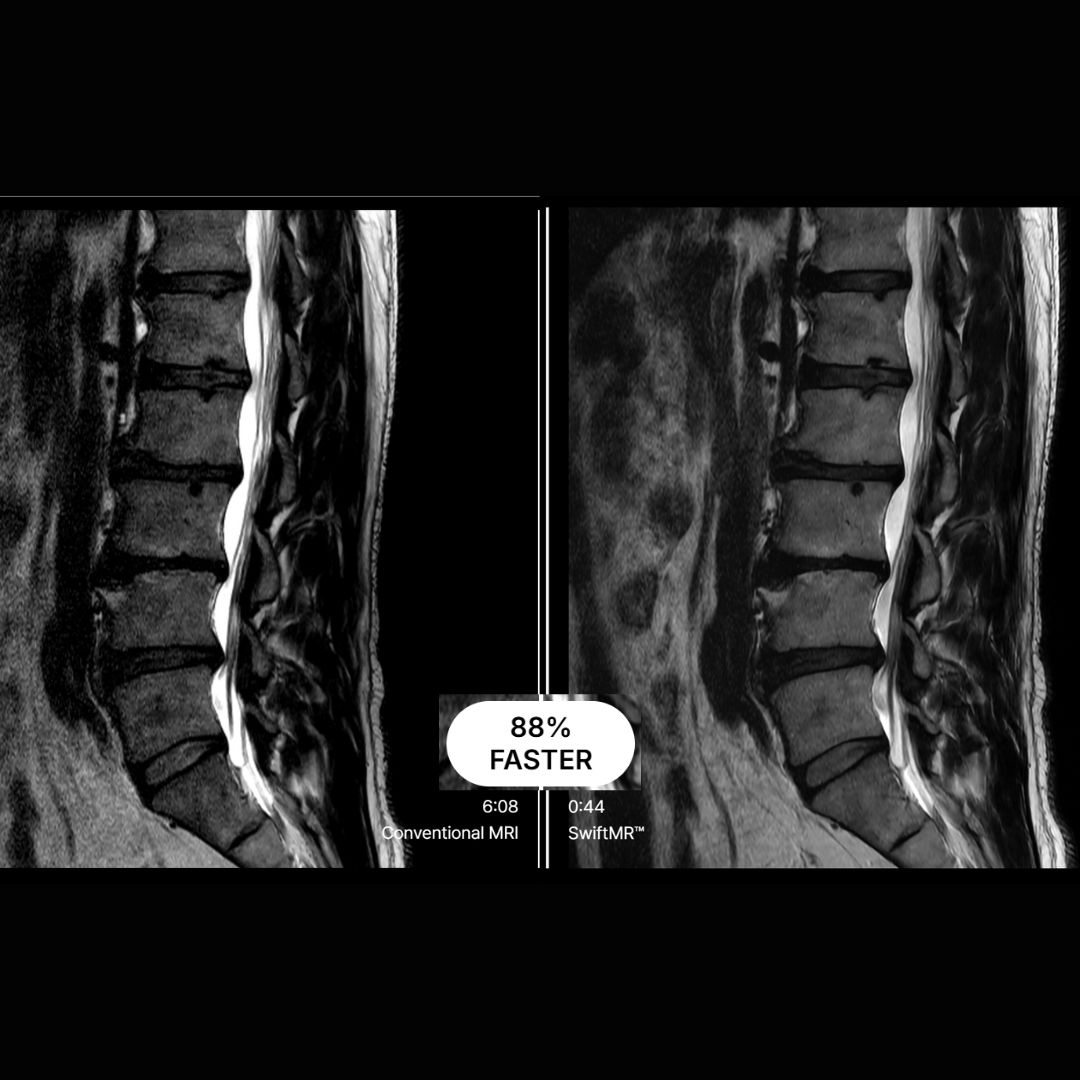

Στον Ιπποκράτη προχωρήσαμε σε μια σημαντική αναβάθμιση: εγκαταστήσαμε την τεχνολογία SwiftMR™ της AIRS Medical, μια καινοτόμο λύση τεχνητής νοημοσύνης (AI) που βελτιώνει τις εξετάσεις Μαγνητικής Τομογραφίας, τόσο στην ταχύτητα όσο και στην ποιότητα εικόνας.

Η SwiftMR™ επιτρέπει εξοικονόμηση χρόνου έως και 50% σε ορισμένα πρωτόκολλα, χωρίς να θυσιάζεται η διαγνωστική ακρίβεια χάρη στους αλγορίθμους AI που βελτιώνουν την ανάλυση και μειώνουν τον απεικονιστικό θόρυβο.

Δείτε μερικά χαρακτηριστικά παραδείγματα στις παρακάτω φωτογραφίες